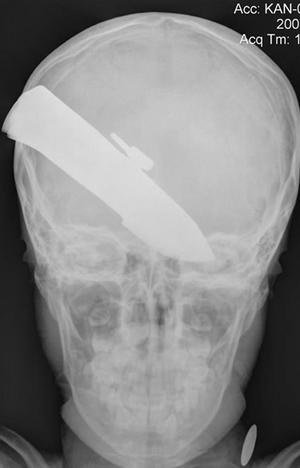

Как сообщает The Sidney Morning Herald, военные хирурги из полевого госпиталя в провинции Гельманд сделали рентгеновский снимок головы мальчугана и выяснили, что в черепе мальчугана застряло 7,5 см закаленной стали. Врачи были в ужасе.

— Лезвие проткнуло черепную коробку в затылочной части. Оно аккуратно прошло между двумя полушариями мозга, не повредив ни одно из них. Поэтому любая попытка вытащить нож из головы ребенка могла просто погубить его, — рассказали военные врачи.

Хирурги провели уникальную операцию и удалили лезвие. По словам отца пострадавшего, все произошло 14 июля 2007 года.